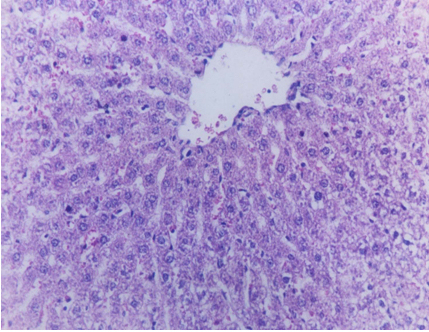

Histopathological results

Our results (Figure 1 [Fig. 1], Figure 2 [Fig. 2], Figure 3 [Fig. 3], Figure 4 [Fig. 4], Figure 5 [Fig. 5], Figure 6 [Fig. 6], Figure 7 [Fig. 7]) revealed that treatment of the PC group with FO or OO supplemented with vitamins E & C led to the best improvement. The histopathological investigation showed apparently normal hepatocytes.

Little data are available on the effect of supplemented diets with vitamin E and C on intoxicated rat livers with CCl4. The histological results confirmed that the hepatically injured rats with CCl4 and fed on supplemented FOEC or OOEC showed apparently normal hepatocytes.